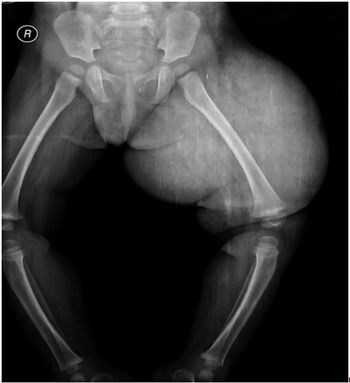

Case History: 2-year-old female with complaints of swelling of vulva, gluteal region, and left thigh since birth.